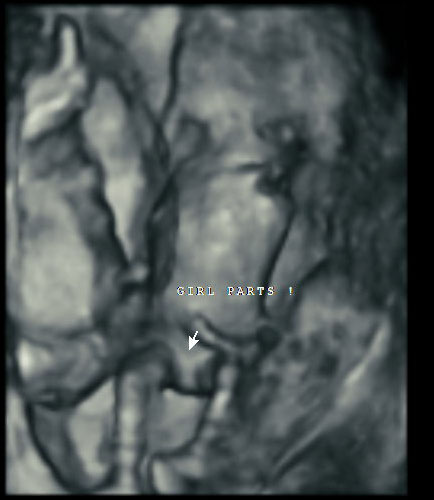

Here’s how ultrasound works in pregnancy: As early as 16 weeks, women can see a “fetal portrait” of their baby and determine its gender. Ultrasound technology has improved dramatically over the decades from flat, grainy black and white images to the current three-dimensional time experience.

How far along do you have to be for a gender scan?

Gender can usually be determined at 16 weeks.